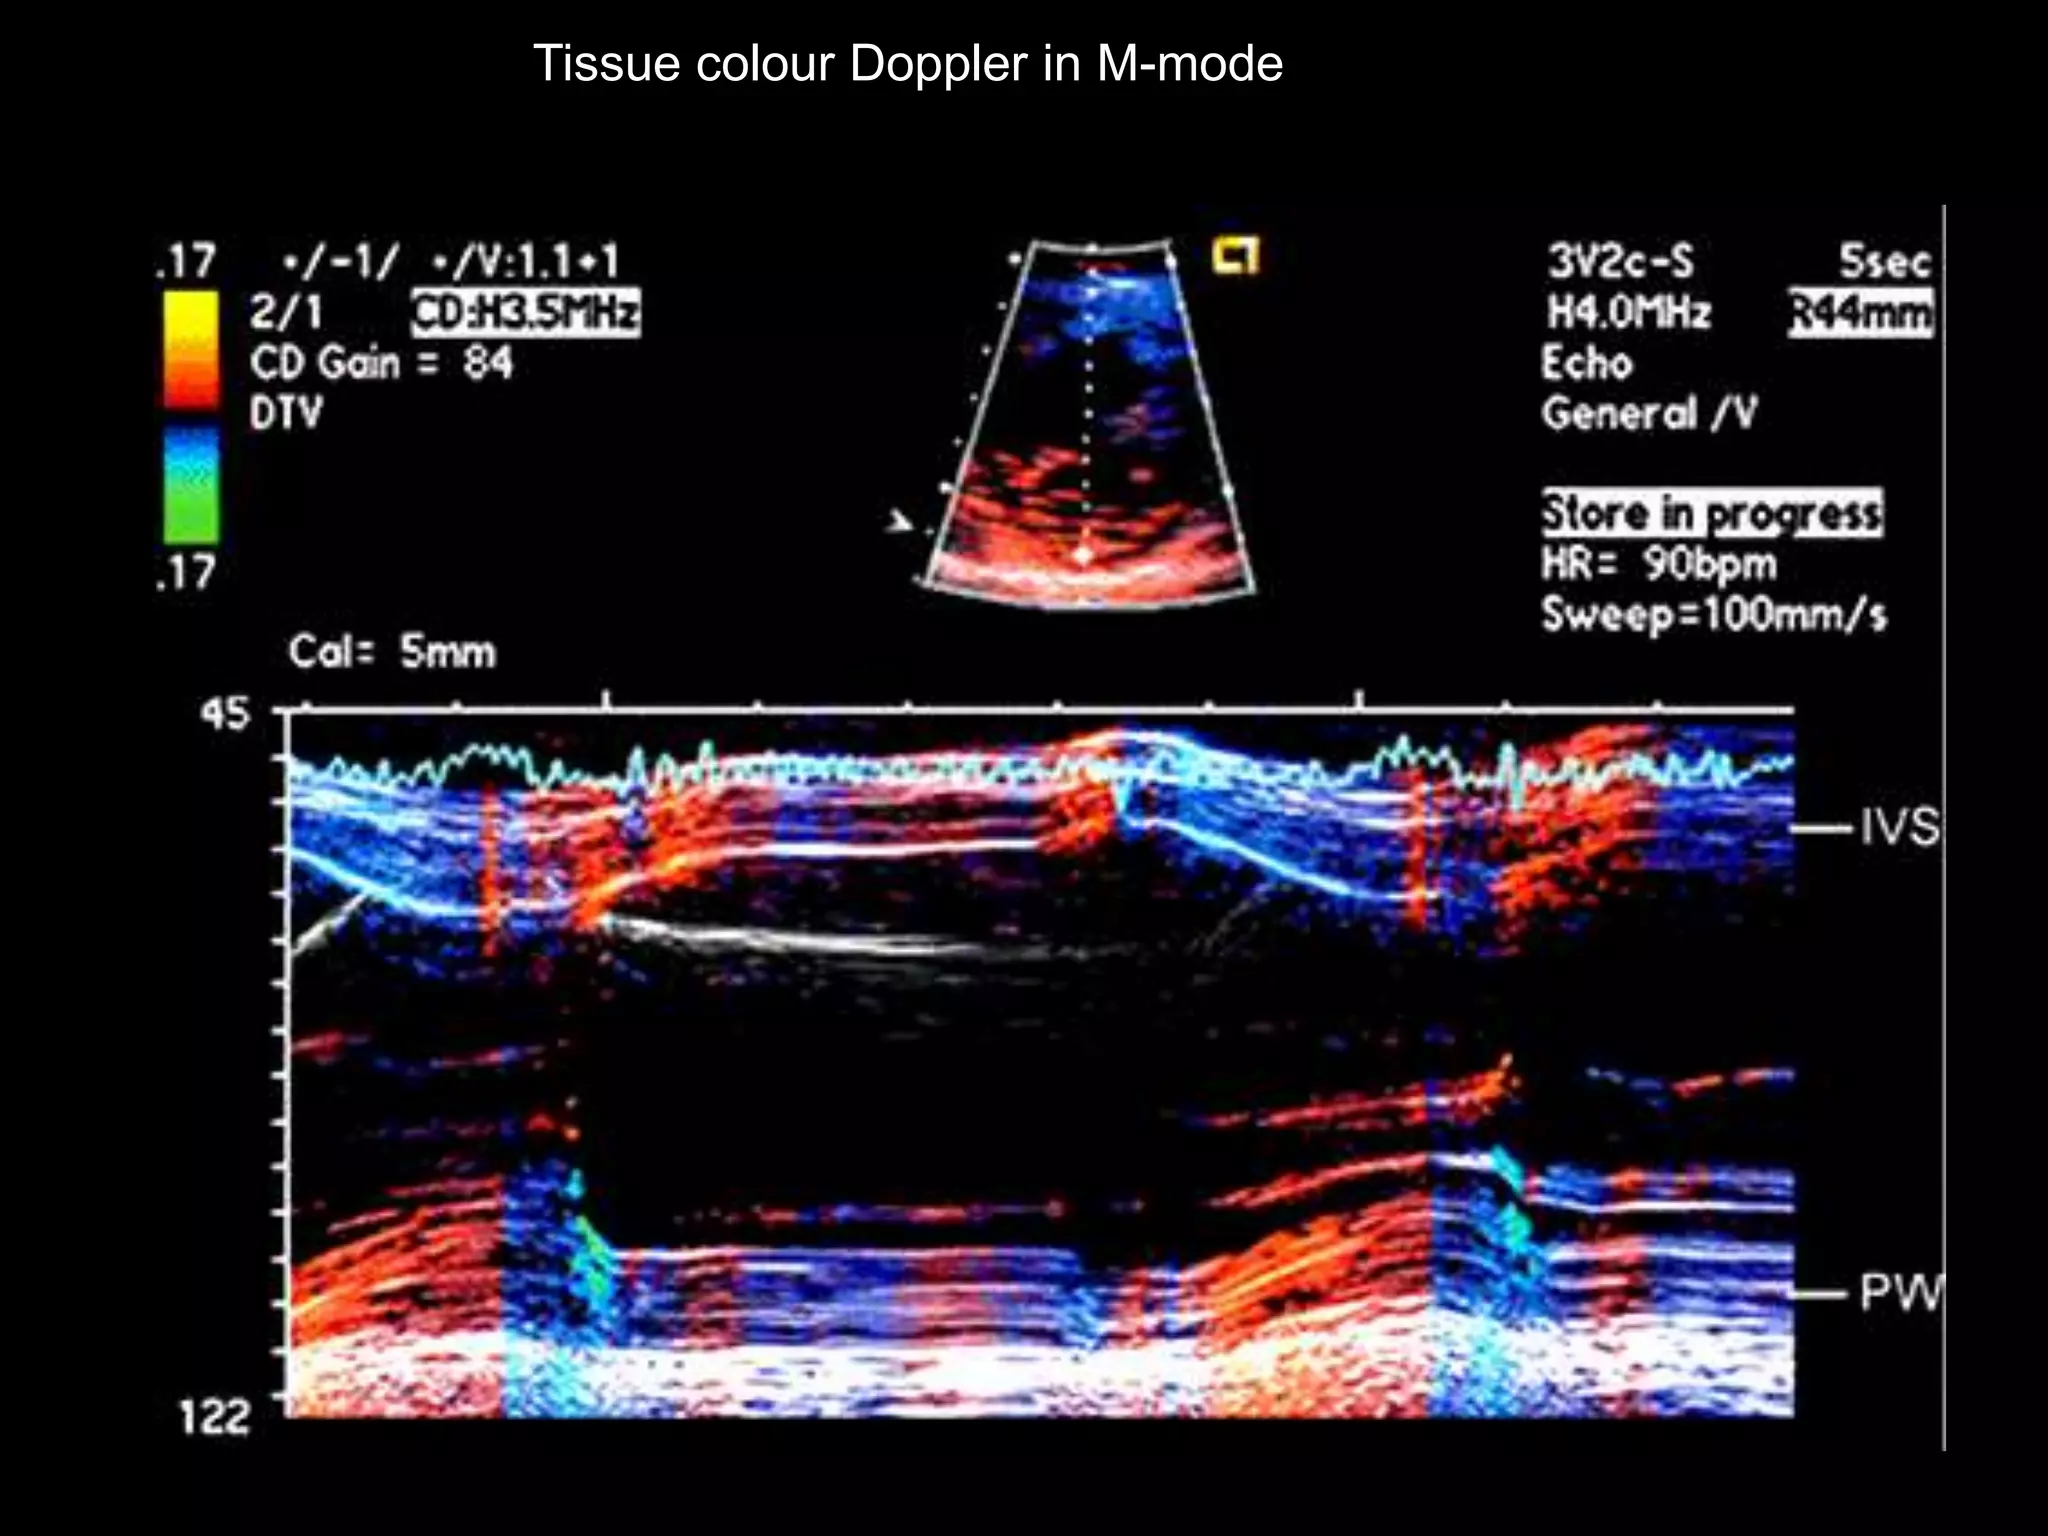

Tissue colour Doppler in M-mode

 byproduct of tissue Doppler imaging

 Basoapical views of each ventricular segment

are displayed as seven color bands, with each

color representing a particular distance the

tissue moves during systole

 Tissue tracking provides a rapid assessment of

systolic motion